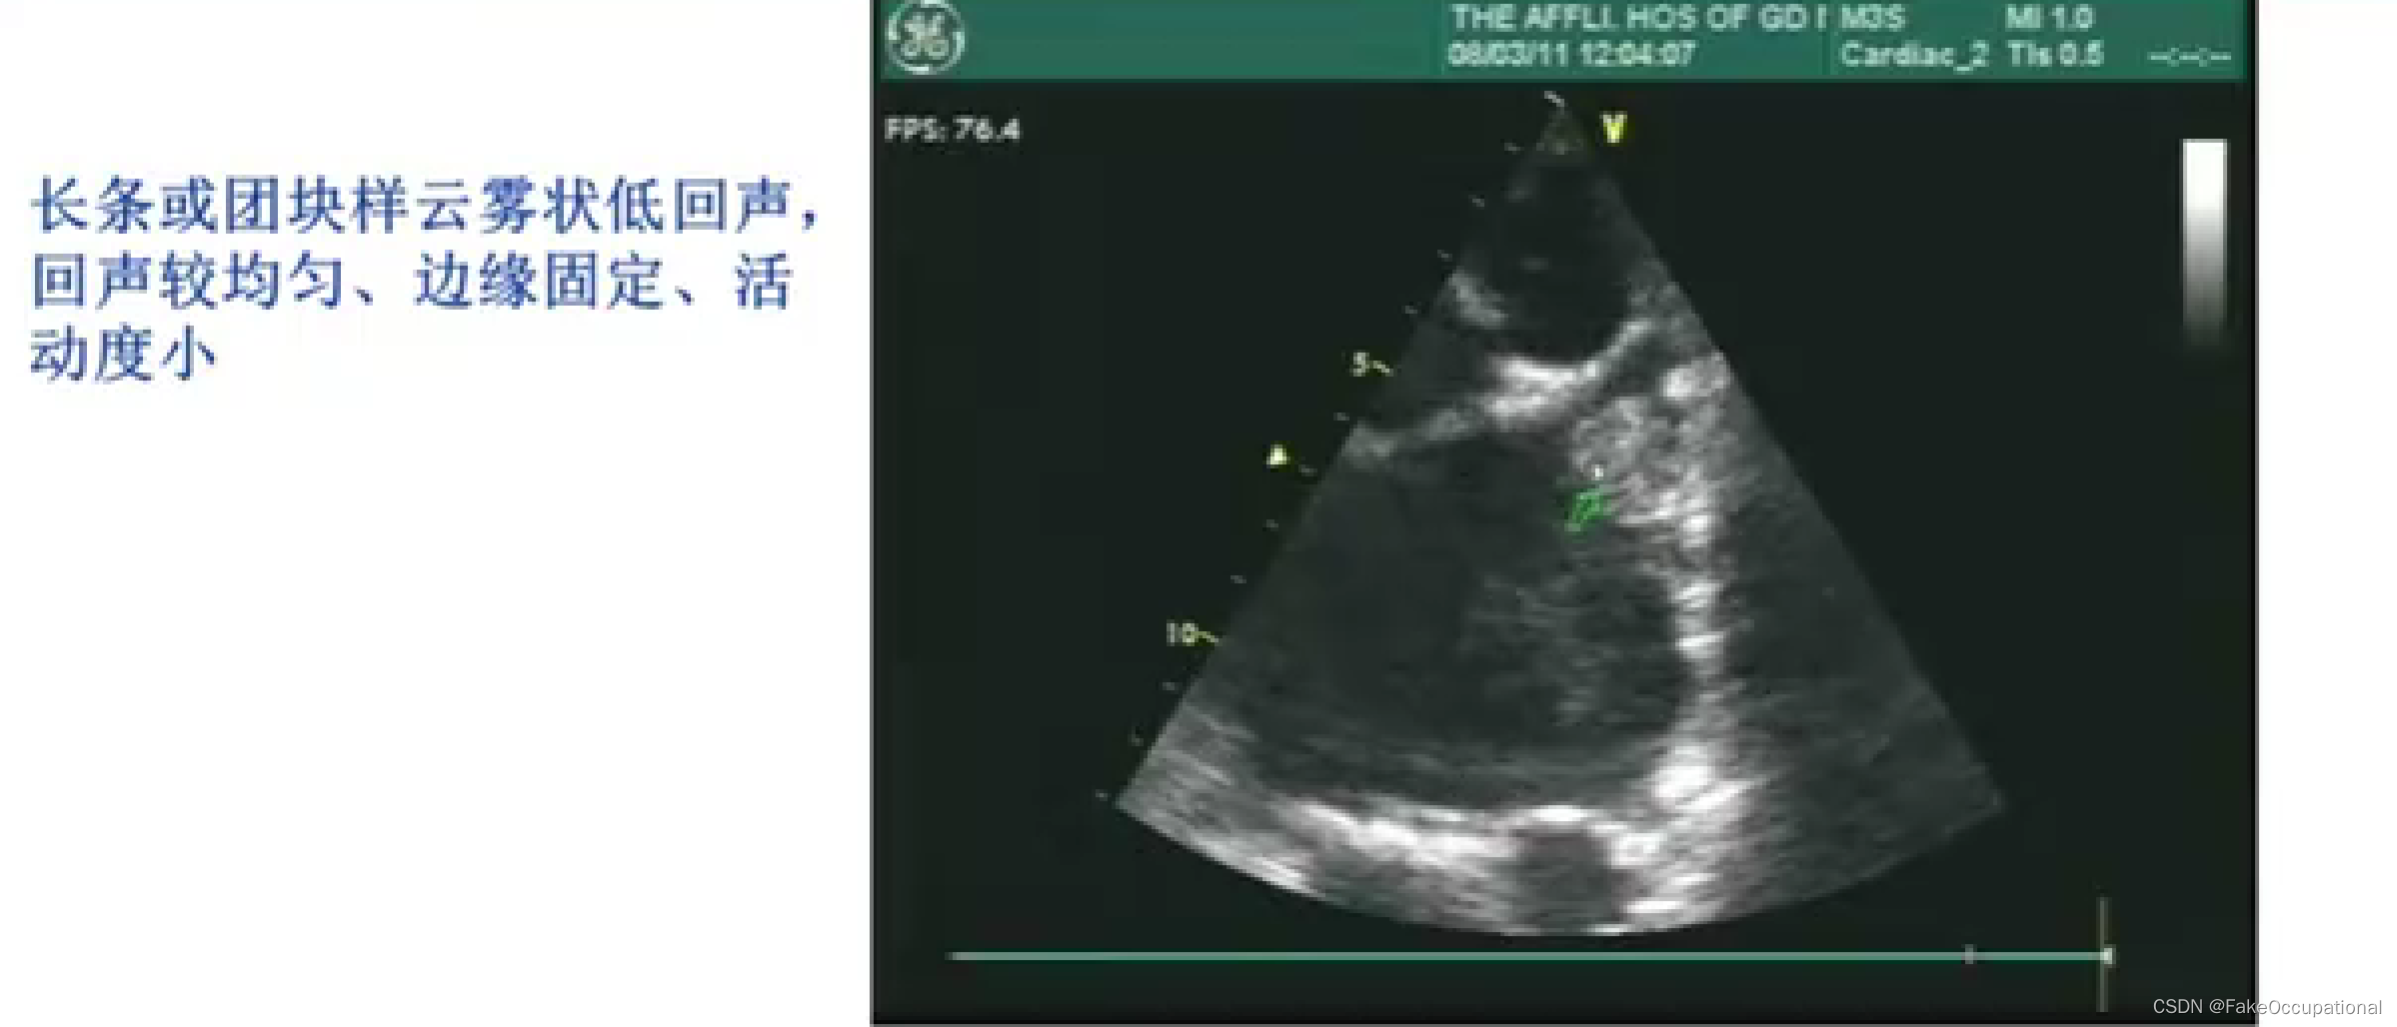

冠心病超声诊断

冠心病的诊断方法

- 心电图

- 心脏核素扫描

- 超声心动图

- 螺旋CT

- 心脏核磁共振

- PET-CT

- 冠状动脉造影 (金标准)

超声新技术在冠心病中的应用